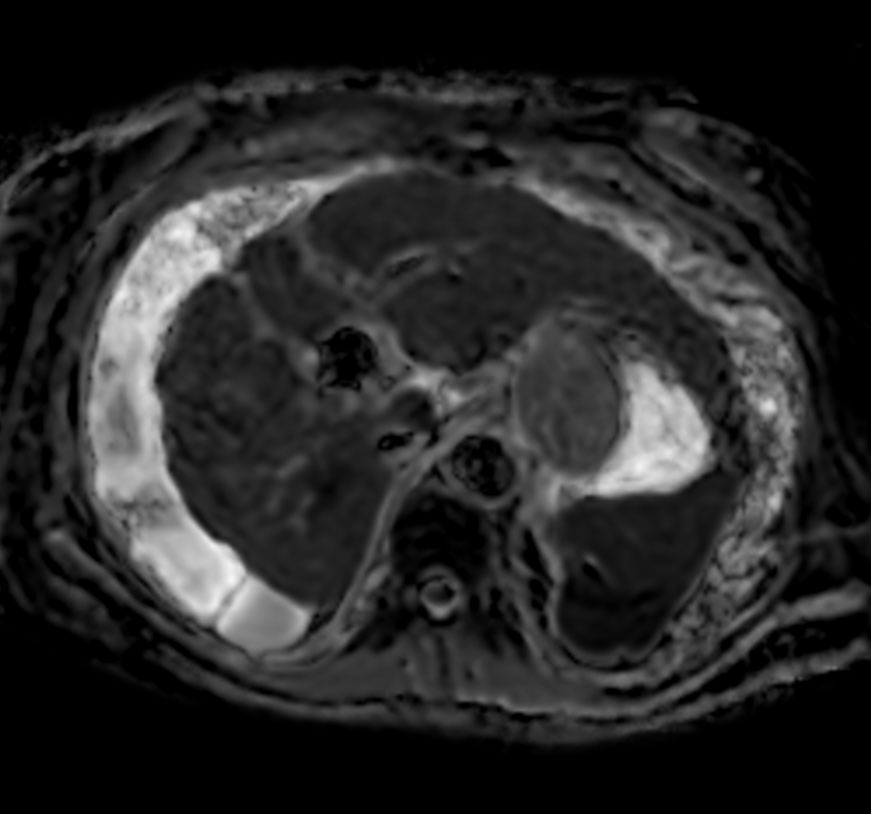

Axial Diffusion - b0